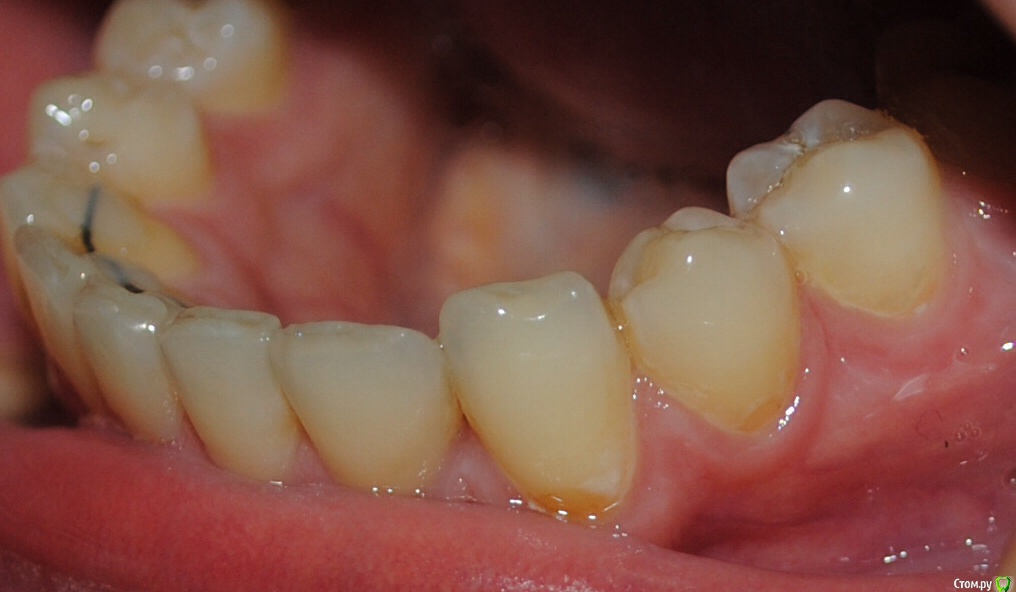

Алина-малина Опубликовано 4 августа, 2015 Поделиться Опубликовано 4 августа, 2015 Здравствуйте, уважаемые специалисты! Подскажите пожалуйста, как можно исправить эту ситуацию? Можно ли обойтись без брекетов? После ношения брекетов стал наклоняться клык вовнутрь. Стоит несемный ретейнер. Ортодонт утверждает что все в порядке и надо делать лоскутную операцию(( Ссылка на комментарий

Yana guapa Опубликовано 4 августа, 2015 Поделиться Опубликовано 4 августа, 2015 Подскажите пожалуйста, как можно исправить эту ситуацию? Можно ли обойтись без брекетов? После ношения брекетов стал наклоняться клык вовнутрь. если клык стал уходить во внутрь - значит что то его туда толкает. как правило, верхний клык (его позиция и наклон). За какой срок произошло изменение после снятие брекетов? Если реально беспокоит - то повторное ношение брекетов с правильным конечным взаимоотношением зубов (если это возможно сделать в силу различных факторов ). Ссылка на комментарий

Алина-малина Опубликовано 15 августа, 2015 Автор Поделиться Опубликовано 15 августа, 2015 Спасибо что ответили. Клык стал уходить через пол года после снятия. Брекеты носила 8 месяцев. Неужели теперь снова брекеты??? Возможно ли хотя бы на одну челюсть? Ссылка на комментарий

Yana guapa Опубликовано 15 августа, 2015 Поделиться Опубликовано 15 августа, 2015 Спасибо что ответили. Клык стал уходить через пол года после снятия. Брекеты носила 8 месяцев. Неужели теперь снова брекеты??? Возможно ли хотя бы на одну челюсть?если на одну челюсть - то и исправится на одной. логично же. а если у Вас на двух челюстях неровно стоят клыки - то на две и ставить надо. чудес не бывает. Вначале выровнять верхнюю, и тогда появится возможность выровнять нижнюю челюсть Ссылка на комментарий